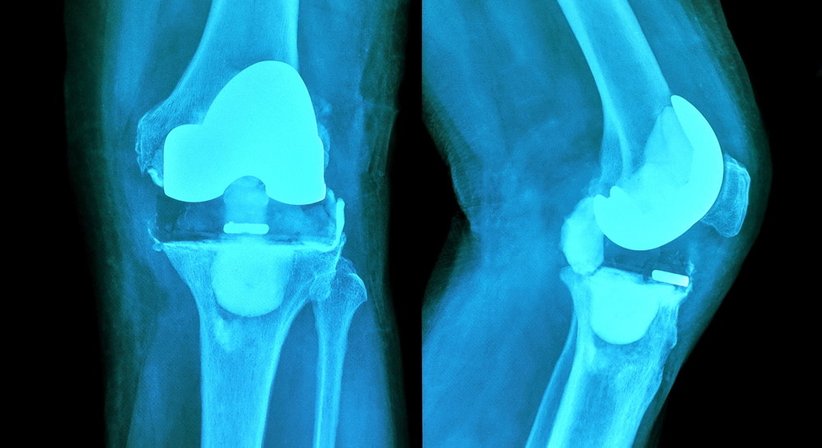

- Knieprothese:

Bei Patienten mit stark fortgeschrittener Kniearthrose, bei welchen mit konservativen Behandlungsverfahren und gelenkerhaltenden Operationsmethoden keine ausreichende Linderung der Beschwerden mehr erreicht werden kann, sollte die Implantation einer Knieprothese in Erwägung gezogen werden.

Eine Knieprothese ahmt die Form und Funktion vom natürlichen Kniegelenk nach und ermöglicht es, Schmerzen und Bewegungseinschränkungen nachhaltig zu beseitigen und die Belastbarkeit vom Knie wiederherzustellen. Unterschieden wird hierbei u. a. zwischen dem vollständigen und dem teilweisen Ersatz vom Kniegelenk - mit einer Teilprothese wird nur ein Teil vom Gelenk ersetzt, das restliche Gelenk bleibt erhalten. Bei Implantation einer Total-Endoprothese wird das gesamte Gelenk durch eine entsprechende Prothese ersetzt. Jeder Knieprothesen-Typ ist in verschiedenen Größen und Varianten verfügbar, was es ermöglicht, die Prothese bestmöglich an die individuellen Bedürfnisse und anatomischen Verhältnisse des Patienten anzupassen.